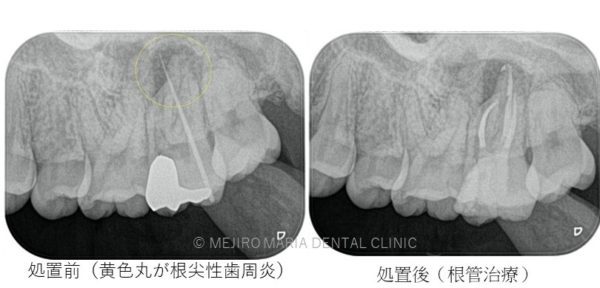

歯髄壊死

歯髄壊死は歯髄に血流がなく、ほぼ全ての歯髄が細菌感染により壊死し、根尖性歯周炎という炎症が根尖まで波及してしまっている状態です。この場合、適切な根管治療を行うことが必要となります。根管治療を行っても治癒に至らない症例に関しては歯根端切除術が必要になります。

根管治療